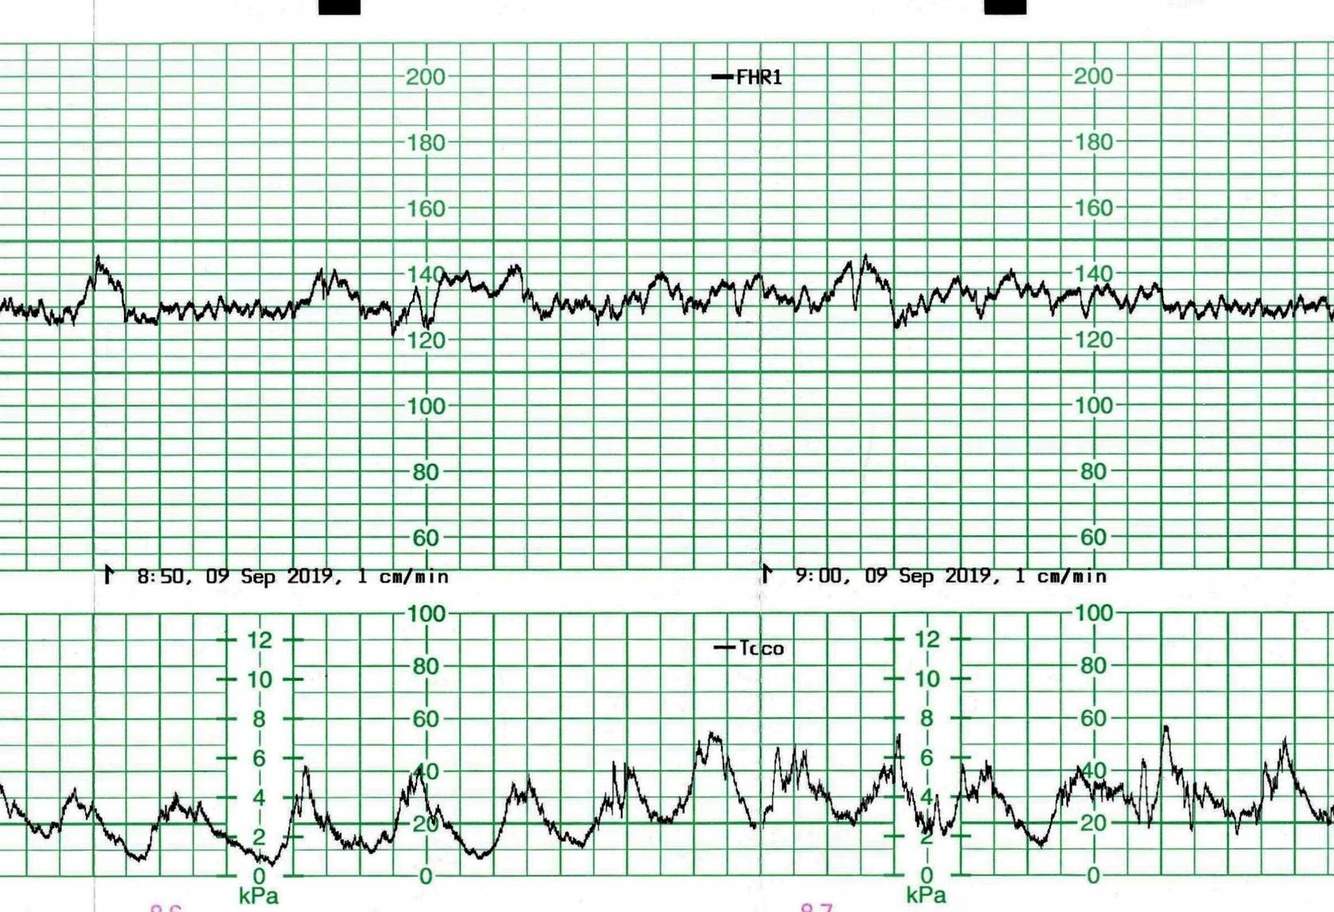

What does this CTG show in regards to the uterine activity?

Tachysystole. It could be classed as

What uterine activity does this CTG show?

Tachysystole, due to the amount of contractions there is not enough rest to adequately oxygenate the fetus. The CTG shows the fetus is well oxygenated but if those contractions continue the fetus will be compromised.